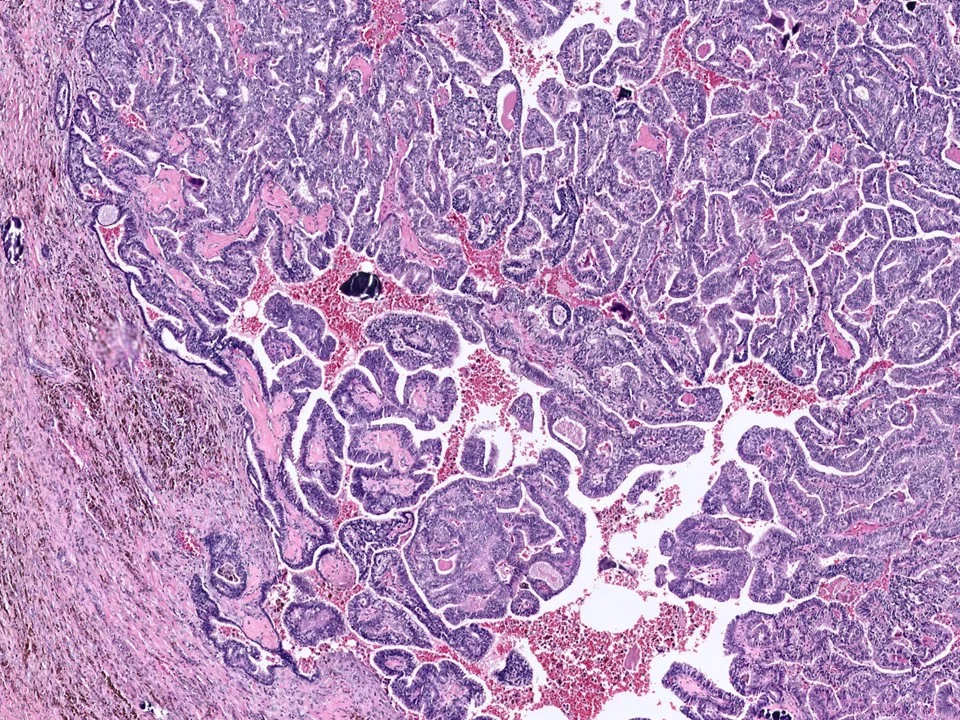

Malignant Phyllodes Tumor

Frond-like projections of cellular stroma covered by epithelium and myopeithelium protruding into epithelial-lined cystic spaces create a leaf-like appearance.

Malignant phyllodes have an infiltrative border (as pictured here), highly cellular stroma, stromal cells with moderate to marked nuclear pleomorphism, and prominent mitotic activity (>/= 10 mits per 10 HPF)

It is difficult to predict the clinical outcome of patients with phyllodes tumors. The major clinical concern is local recurrence, with distant metastases being uncommon. The presence of malignant heterologous elements appears to be indicative of a poorer prognosis. Of note, phyllodes tumors spread hematogenuosly, not by lymphatics, so LN dissection is not indicated.